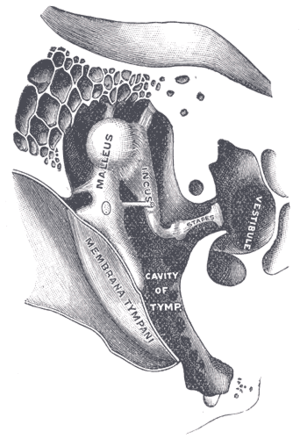

External and middle ear, opened from the front. Right side. Chain of ossicles and their ligaments, seen from the front in a vertical, transverse section of the tympanum.

Chain of ossicles and their ligaments, seen from the front in a vertical, transverse section of the tympanum. Ossicles

Ossicles Tympanic cavity. Facial canal. Internal carotid artery.